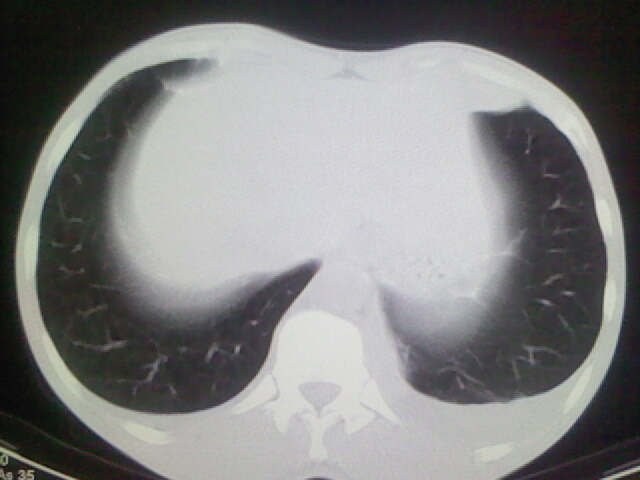

以下是引用杀毒软件在2008-9-3 6:11:00的发言:[br]侵袭性胸腺瘤------一般不侵到气管旁[br][br]考虑----纵隔淋巴瘤,心包及胸膜受累

以下是引用随光逐影在2008-9-3 7:07:00的发言:[br]1)考虑淋巴瘤可能。2)双侧胸腔积液(以左侧为甚)。3)心包积液。